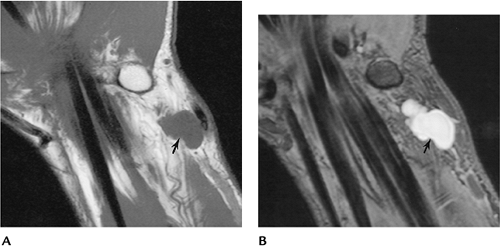

FIGURE 9-54 Fibrolipoma of the ulnar nerve. Axial T1-weighted images (A,B) demonstrate an enlarged low signal intensity nerve with associated fatty tissue (arrow).